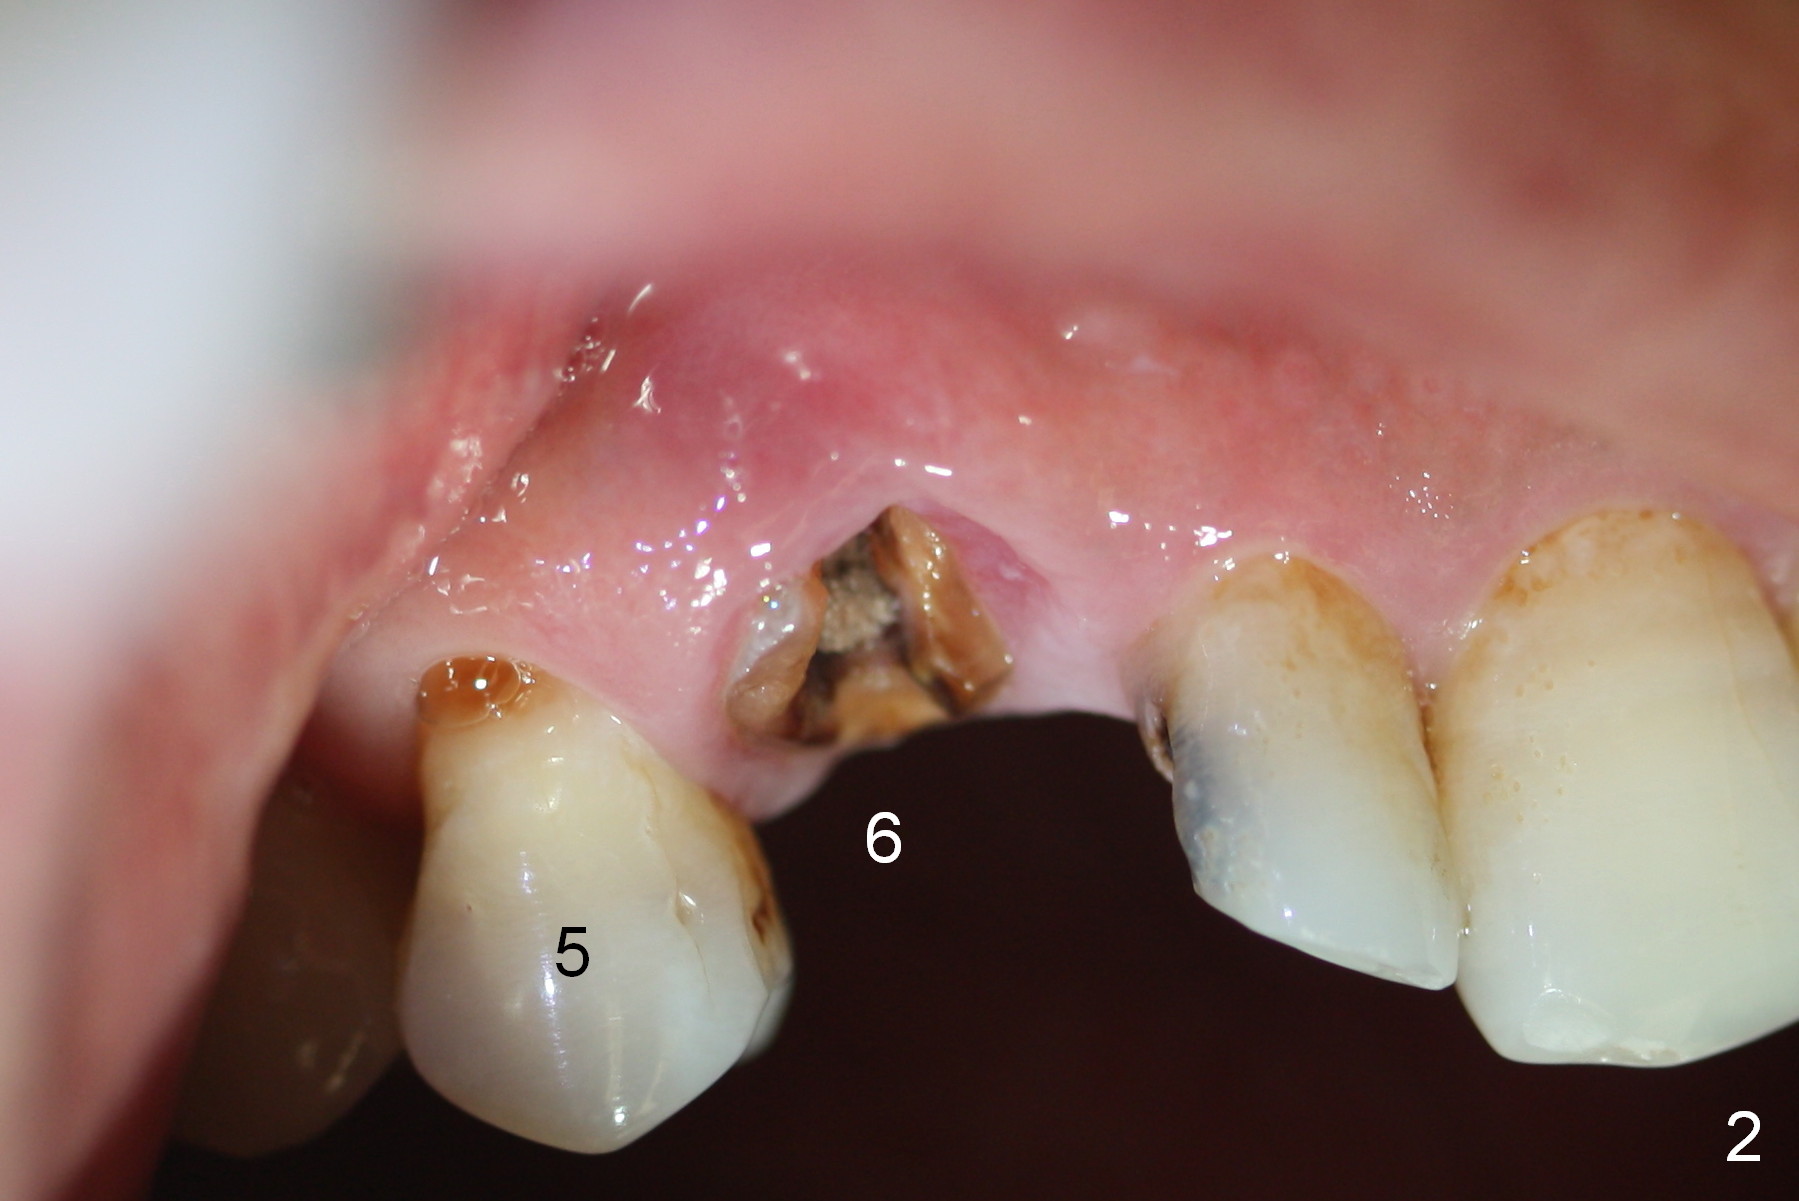

While the periodontal ligament is being severed with Proximators (periotomes), the tooth #6 is found closer to the tooth #5 (Fig.1,2). When the tooth is extracted, an osteotomy is initiated slightly mesially in the palatal wall of the socket (Fig.3 O).